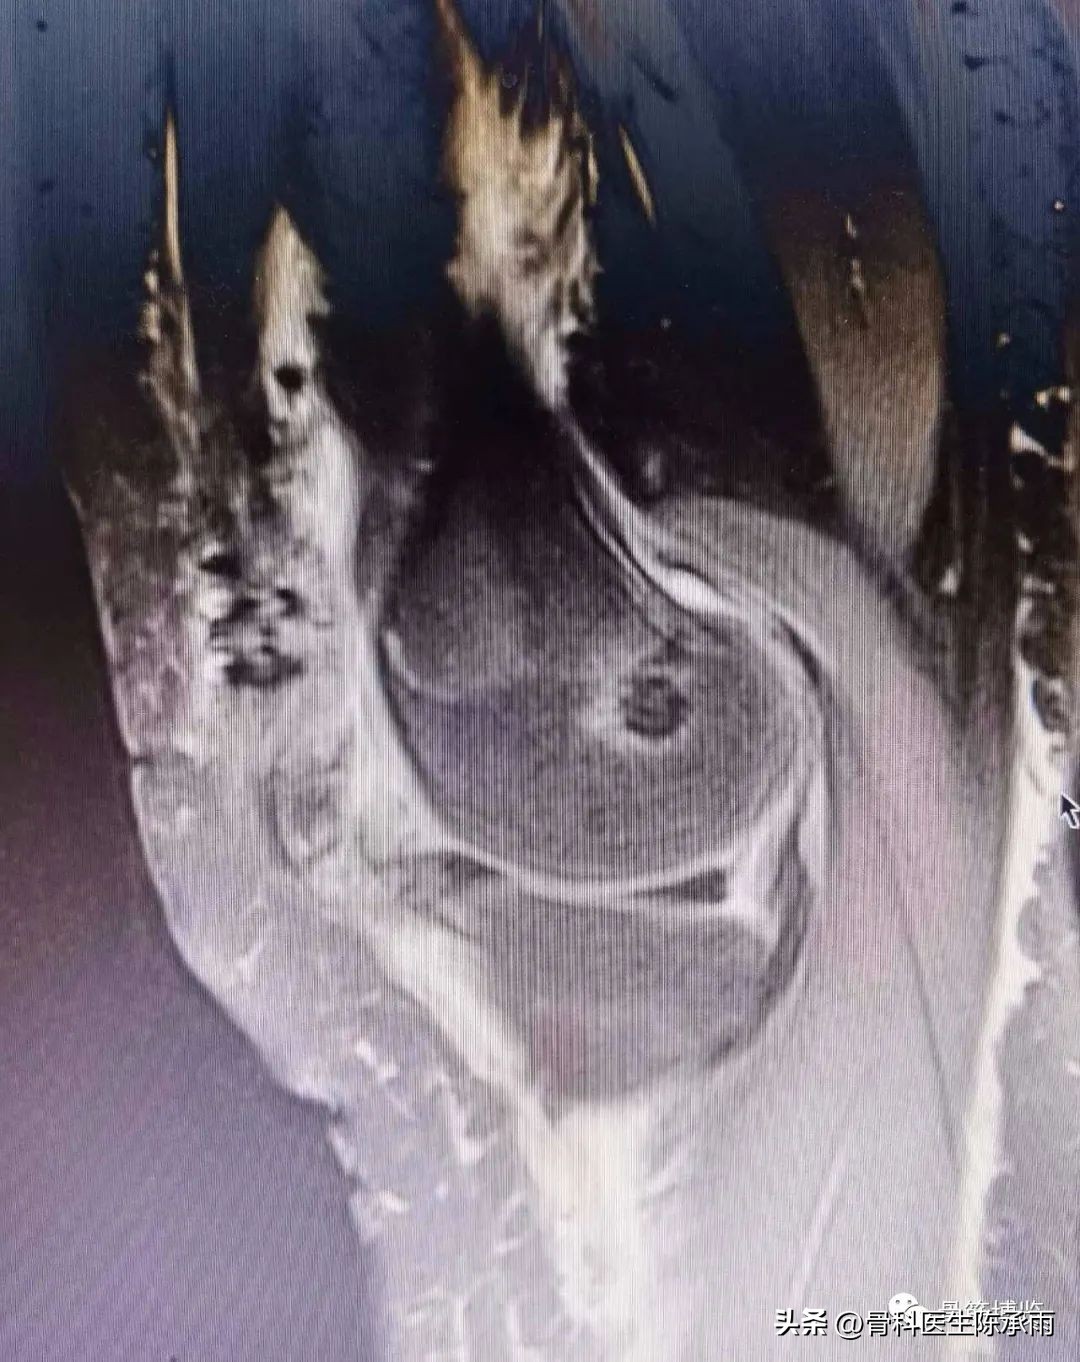

术前影像